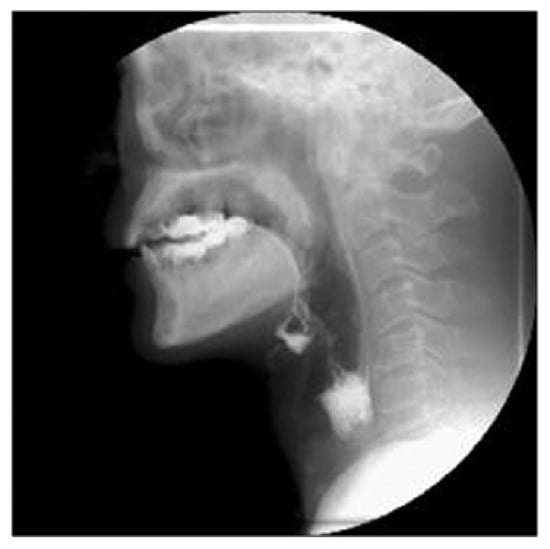

- Dodds, W.J.; Logemann, J.A.; Stewart, E.T. Radiologic assessment of abnormal oral and pharyngeal phases of swallowing. AJR Am. J. Roentgenol. 1990, 154, 965–974. [Google Scholar] [CrossRef] [PubMed]

- Pikus, L.; Levine, M.S.; Yang, Y.X.; Rubesin, S.E.; Katzka, D.A.; Laufer, I.; Gefter, W.B. Videofluoroscopic studies of swallowing dysfunction and the relative risk of pneumonia. AJR. Am. J. Roentgenol. 2003, 180, 1613–1616. [Google Scholar] [CrossRef] [PubMed]

- Terré, R.; Mearin, F. Evolución de la aspiración laringo-traqueal en la disfagia orofaríngea secundaria a lesión cerebral traumática: Cuantificación videofluoroscópica [Videofluoroscopy quantification of laryngotracheal aspiration outcome in traumatic brain injury-related oropharyngeal dysphagia]. Rev. Esp. Enferm. Dig. 2007, 99, 7–12. [Google Scholar] [CrossRef][Green Version]